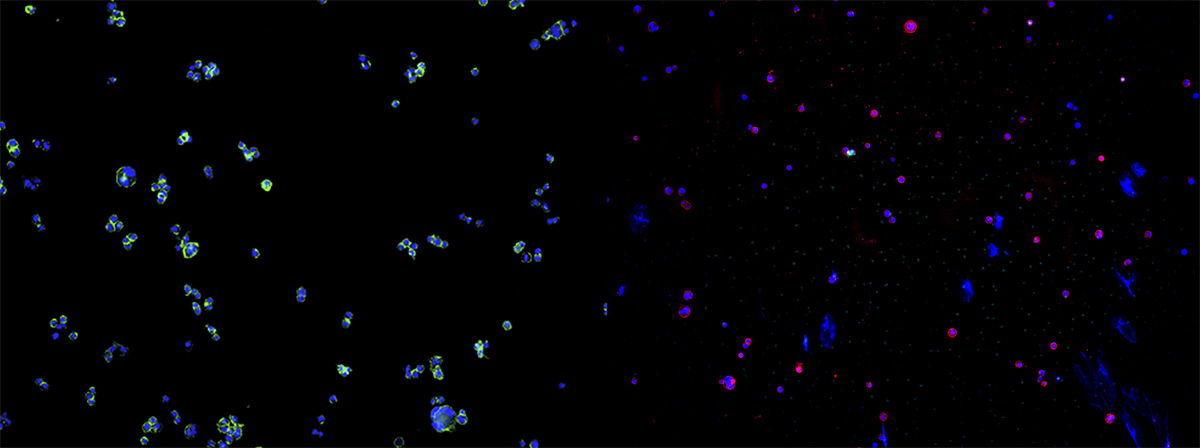

多通道图像融合分析